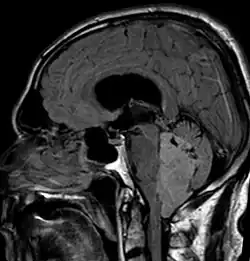

Ependymoma of 4.ventricle in MRI. -

Ependymoma of 4.ventricle in MRI. Left without, right with contrast-enhancement.